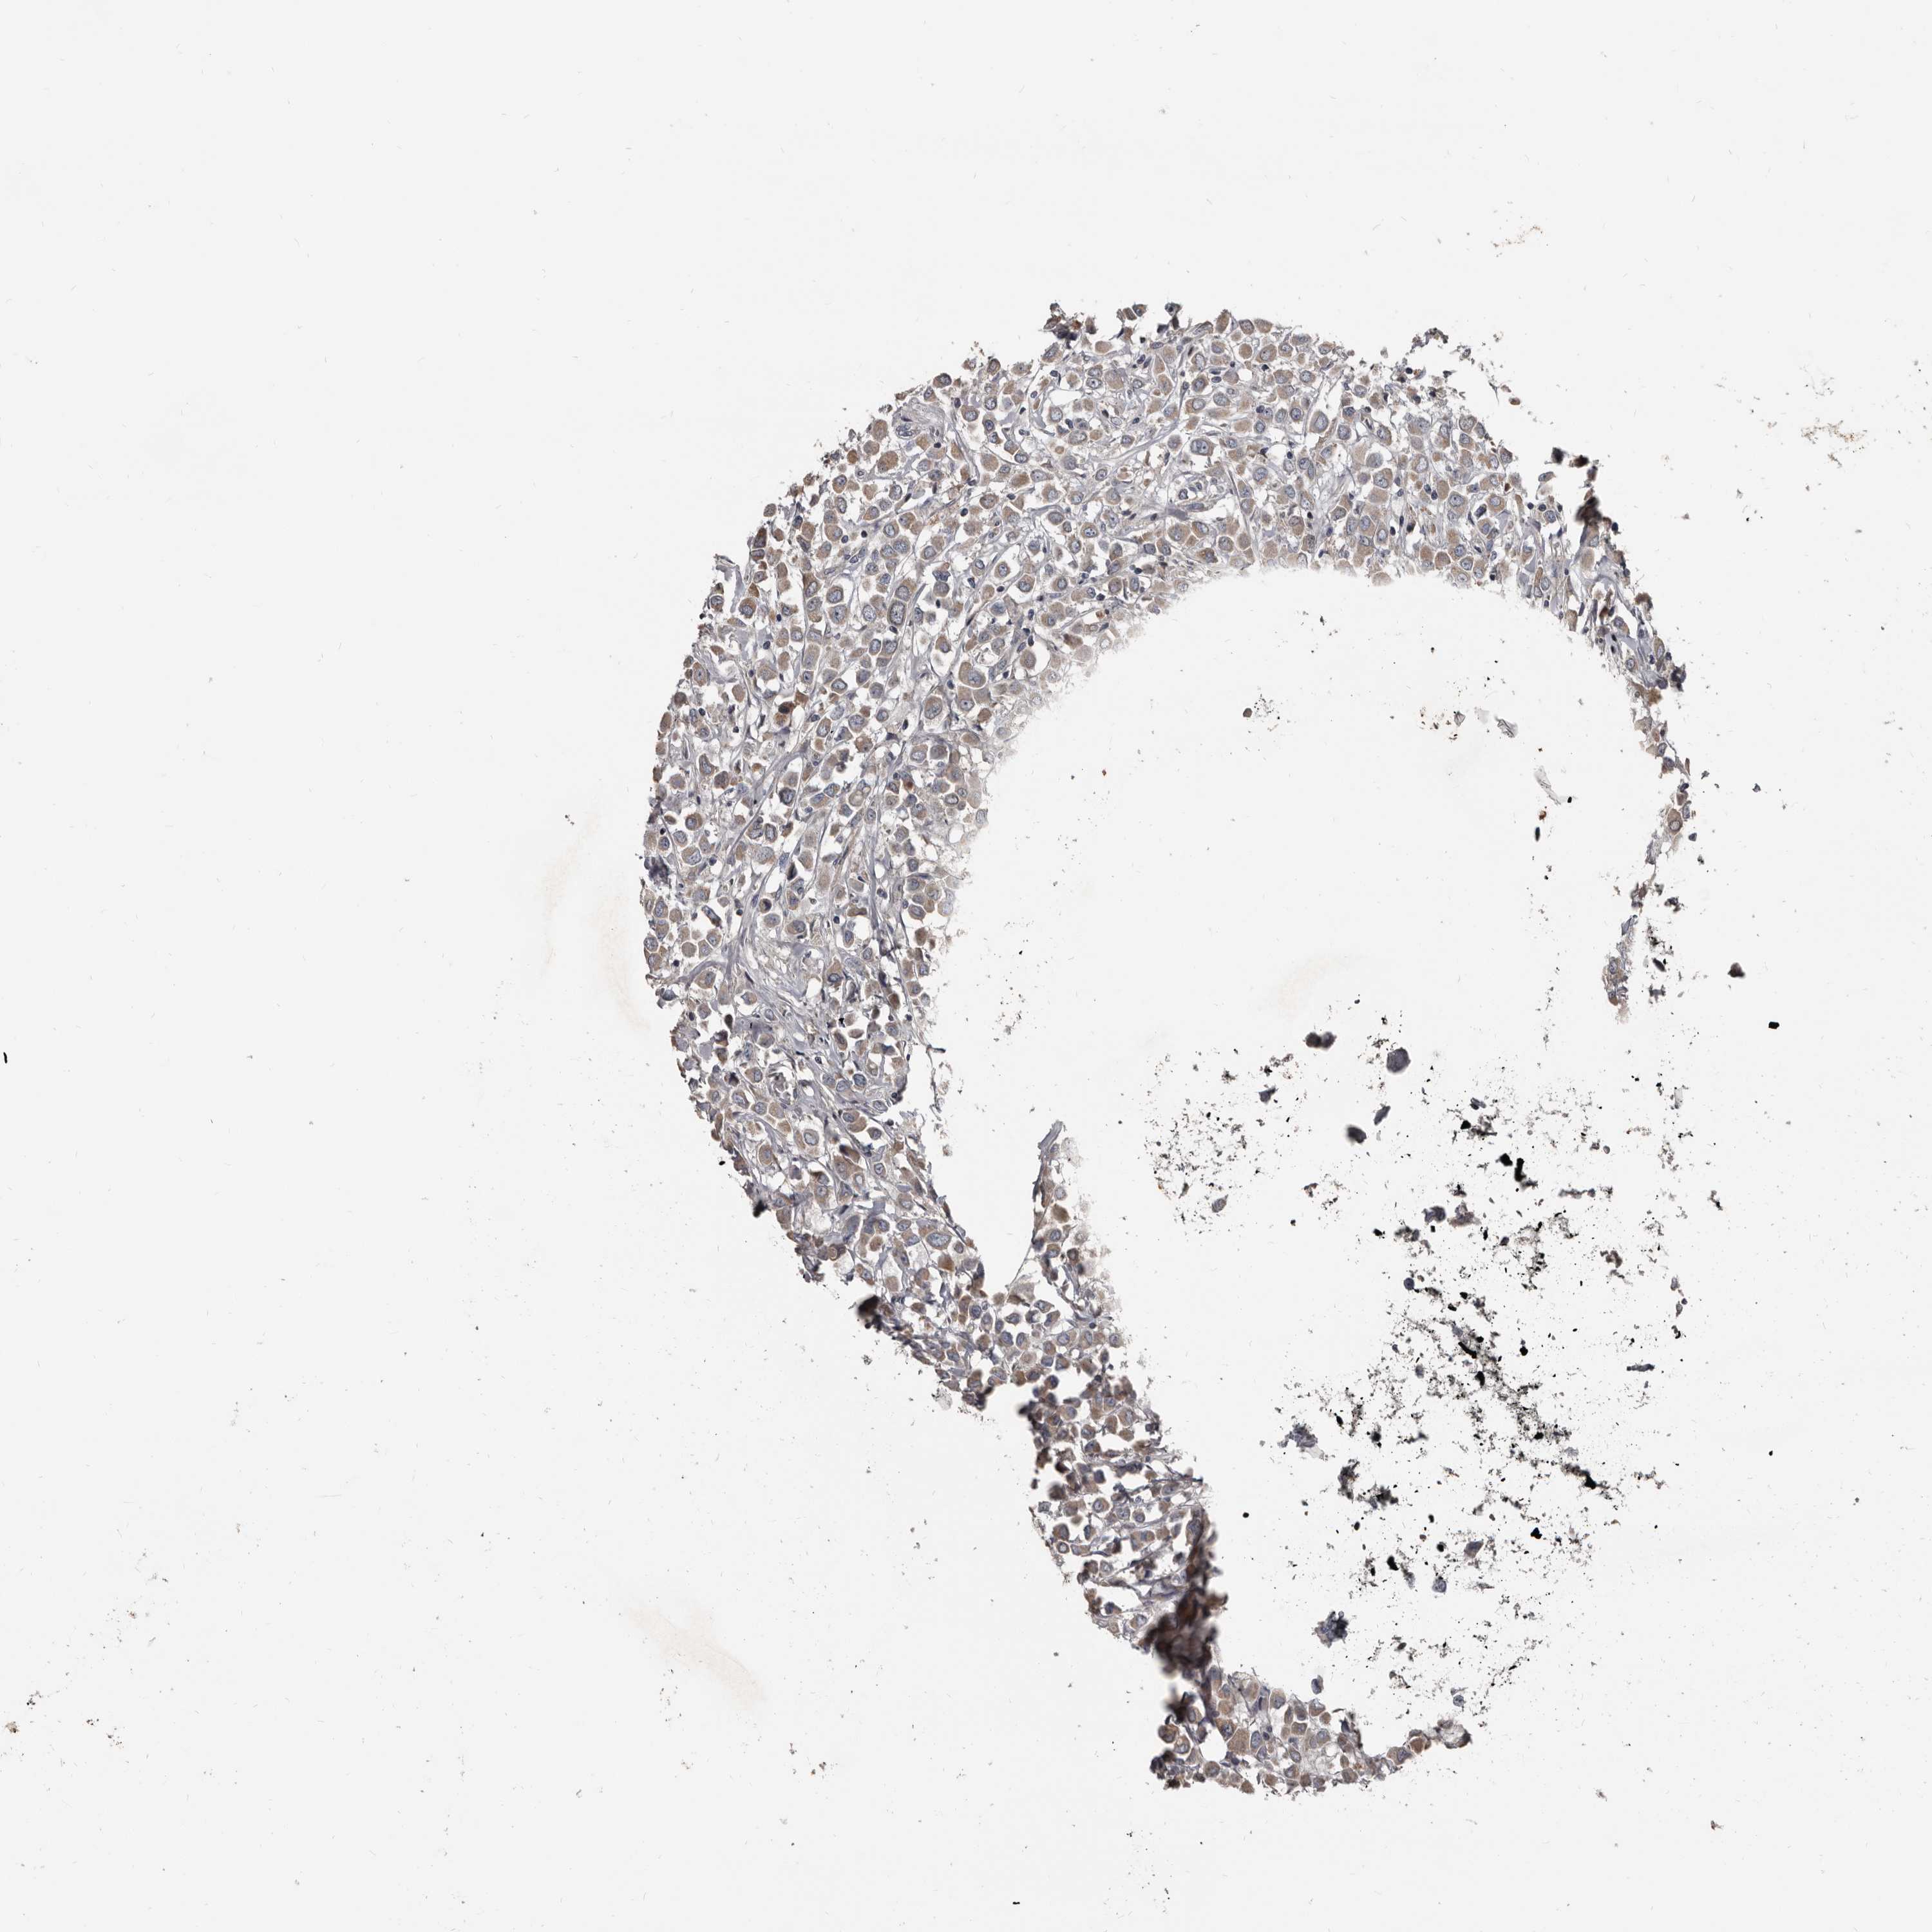

CANCER BREAST CANCER Show tissue menu

BRCA TCGA BRCA VALIDATION PROTEIN EXPRESSION